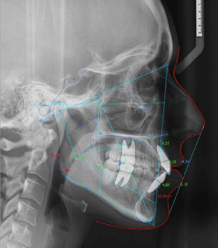

Intraoral Scan Segmentation

Automatic end-to-end segmentation of intraoral scans in seconds.

- Manual tasks are time-consuming, tedious, and expertise dependent

- Orthodontists need to segment teeth and annotate anatomical landmarks

- Our solution delivers automatic end-to-end processing in seconds